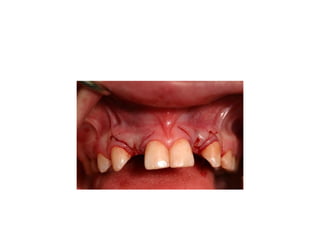

time of insertion

retainer has been modified

final crowns are delivered